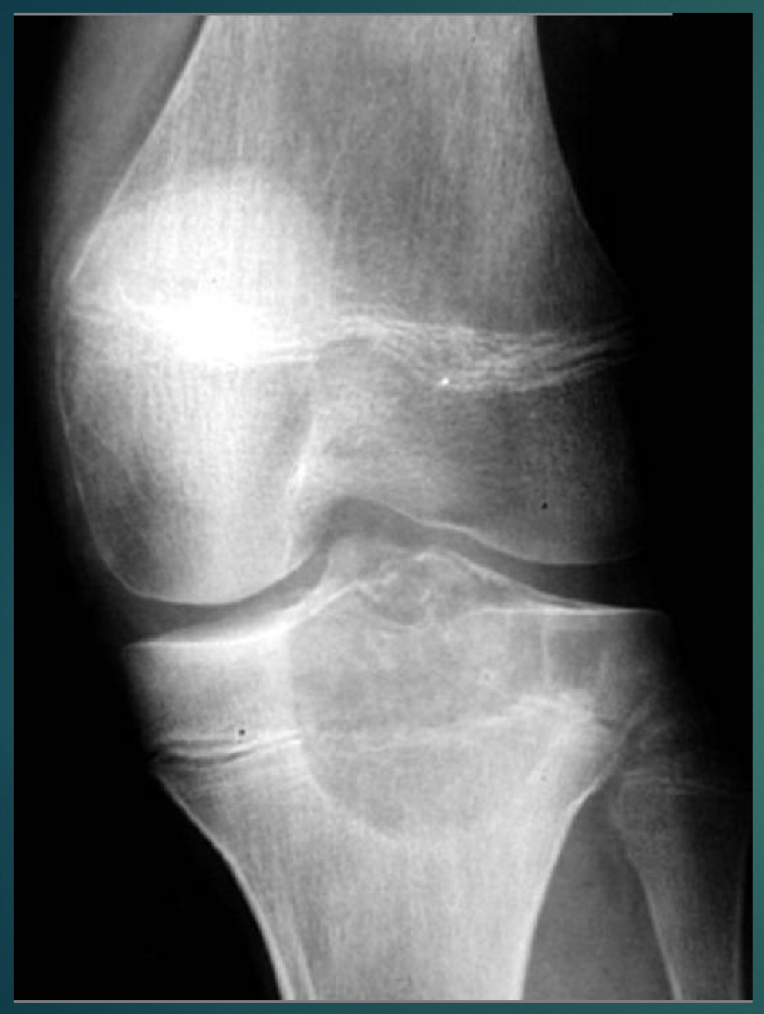

45 YO F. Recently developed knee pain.

• Popcorn like lesion, stippled at proximal tibia.

Think:

• Enchondroma. (Painless)

• Chondrosarcoma (because Pain)